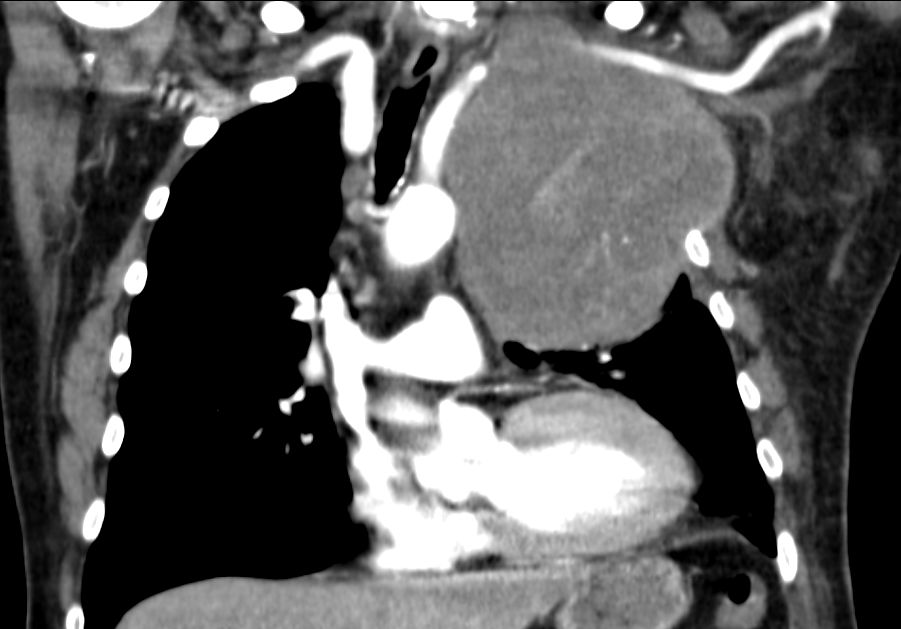

| Pancoast linker Oberlappen | 63-jähriger Mann mit einem Plattenepithelkarzinom

des linken Lungenoberlappens. Klinisch faustgroßes Vorwölbung über dem

linken Schlüsselbein.![]() |

Die Infiltrate haben die A. subclavia

eingeschlossen. Klinisch schlaffe Lähmung des linken Arm mit lividität.

Zusätzlich Verengung des Lidspaltes links.![]() | |